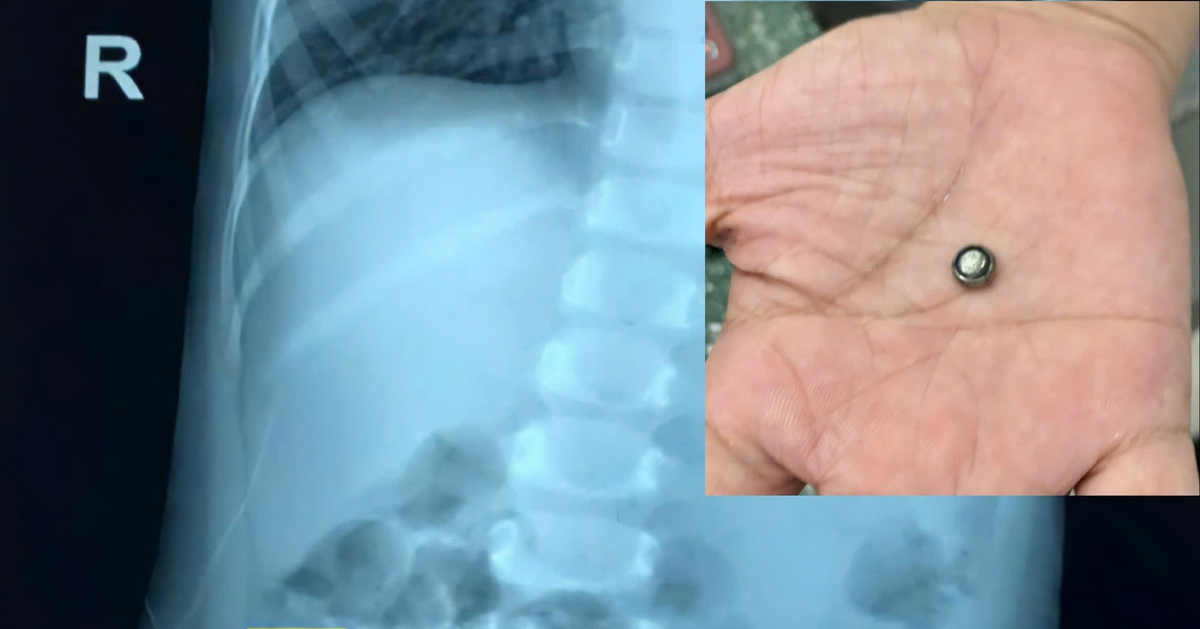

Bé gái 37 tháng tuổi nhập viện do nuốt pin trong đồ chơi điện tử - Tuổi Trẻ Online

Bệnh viện Đa khoa khu vực Cai Lậy, tỉnh Tiền Giang cho biết vừa xử lý kịp thời trường hợp một bé gái 37 tháng tuổi nhập viện do nuốt pin trong đồ chơi điện tử.